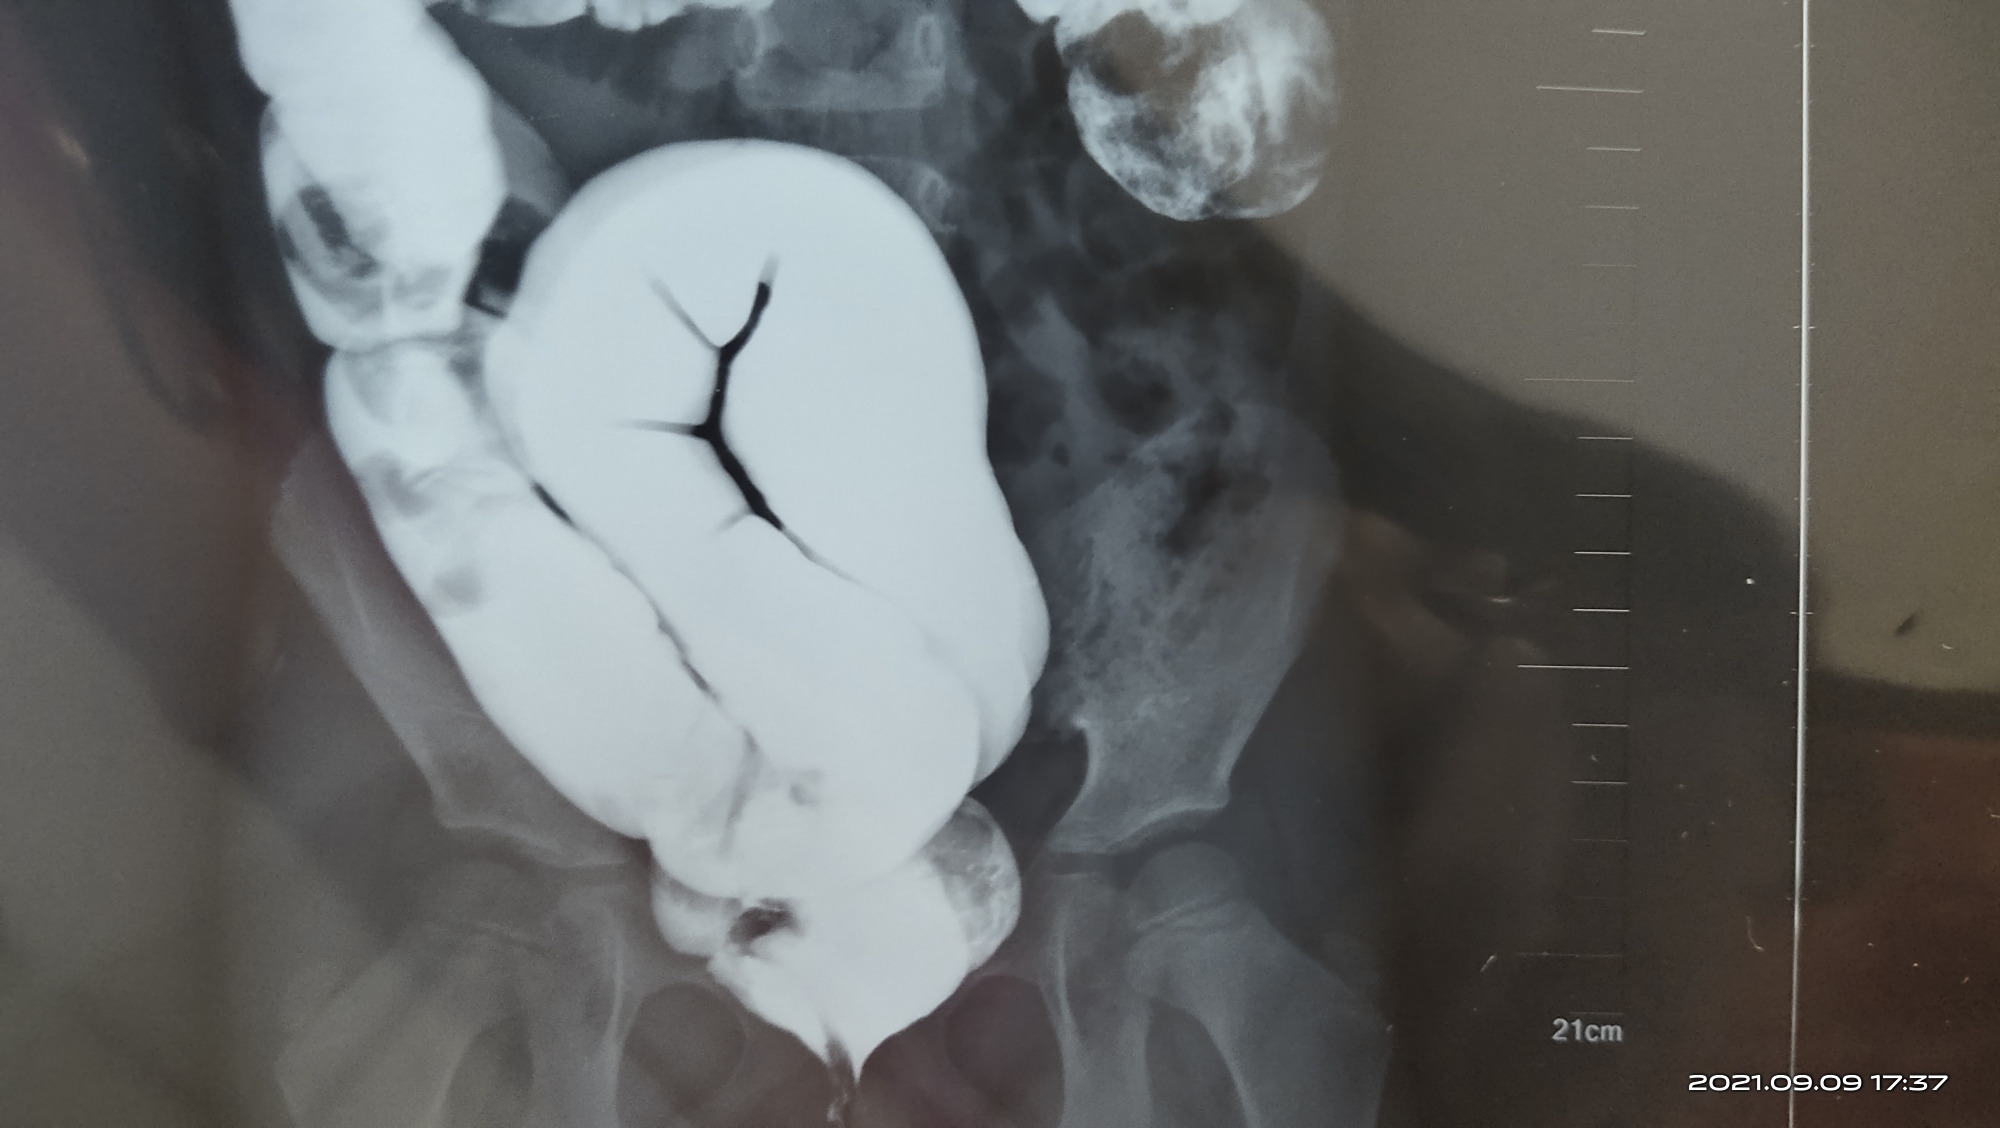

继发性小肠淋巴管扩张症1例

患者入院前腹部x光片,提示肠管梗阻,扩张